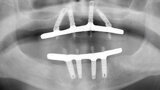

Fig. 7. Rx Pre-operatoria, Prótesis híbrida inmediata con 10 años de evolución y Rx Control a los 10 años.

Fig. 8. Rx Pre-operatoria, Prótesis híbrida inmediata con 10 años de evolución y Rx Control a los 10 años.

Fig. 9. Rx Pre-operatoria, Prótesis híbrida inmediata con 10 años de evolución y Rx Control a los 10 años.